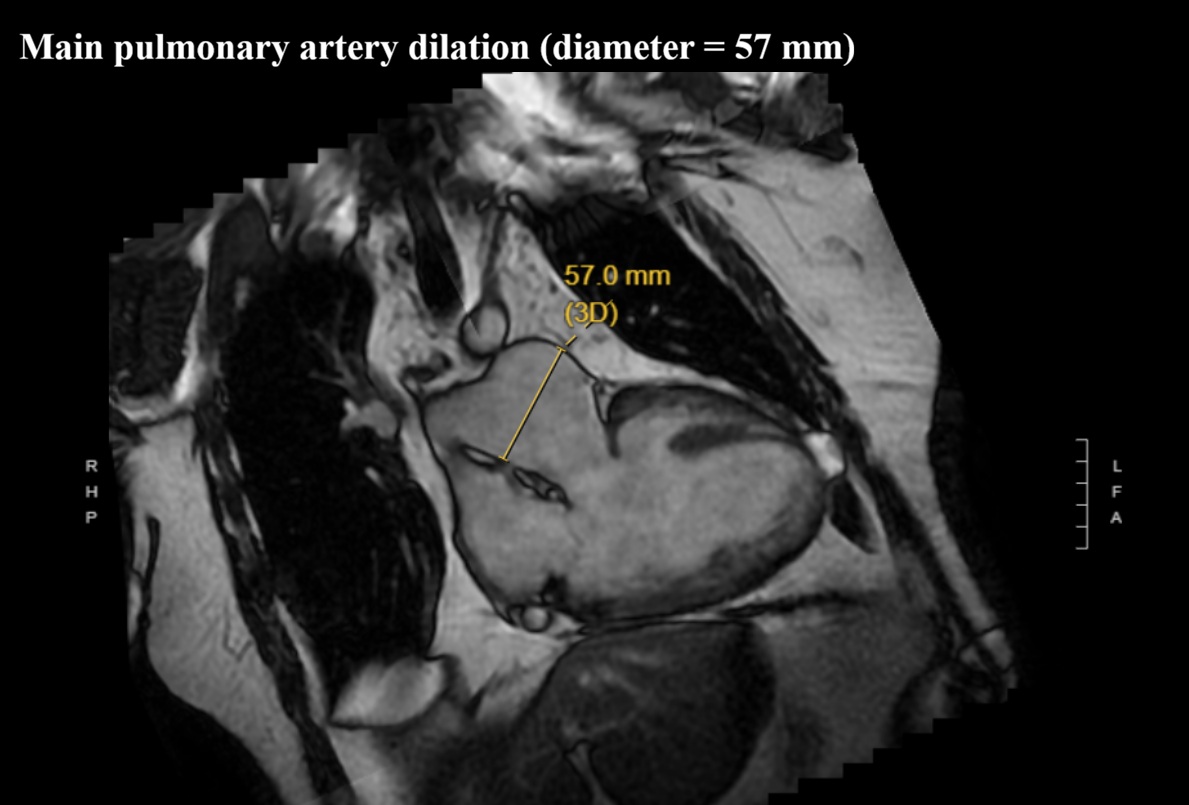

We report a 61-year-old man with unrepaired single-ventricle physiology (double inlet left ventricle, mesocardia, malposed great vessels) and stable chronic cyanosis (baseline SpO2 80–85%). In the absence of a “protective” pulmonary stenosis, lifelong high pulmonary flow and pressure led to pulmonary vascular remodeling and increased resistance, resulting in severe pulmonary arterial hypertension (PAH) with Eisenmenger-type physiology; the single ventricular pump is highly preload-, cardiac rhythm-, and systemic pressure–dependent. The course is complicated by acquired ischemic heart disease: an anterior acute coronary syndrome in 2015 in the setting of anomalous coronaries and supply–demand mismatch. Cardiac MRI showed severe dominant-ventricle dilation, EF ~33%, and antero-apical subendocardial late gadolinium enhancement. Right-heart catheterization confirmed severe PAH with PAP 120/22 mmHg (mean 55), PAWP 9 mmHg and PVR 6.2 WU, supporting initiation of triple PAH therapy (macitentan, sildenafil, selexipag) with close monitoring of systemic pressure and volume status. Clinical decompensations were triggered by atrial fibrillation or atrial tachycardia with high ventricular response, managed with rhythm and/or rate control (amiodarone, digoxin, cautious beta-blocker titration) and tailored decongestion. Non-invasive ventilation with positive pressures (BiLevel) was set conservatively given the effects of intrathoracic pressure on venous return and pulmonary circulation. Long survivors with DILV in natural history are exceedingly rare and appear to cluster into two phenotypes: “balanced” circulations with restricted pulmonary flow, and exceptional cases without protection who develop pulmonary vasculopathy. This patient belongs to the latter and is notable for triple PAH therapy; depressed systolic function may have mitigated pulmonary flow overload, contributing to a fragile equilibrium. Arrhythmic/sudden-death risk stratification in a single ventricle with scar led to ICD counselling, which the patient refused. Unrepaired DILV reaching the sixth decade with severe PAH is exceptional; management should remain physiology-driven.